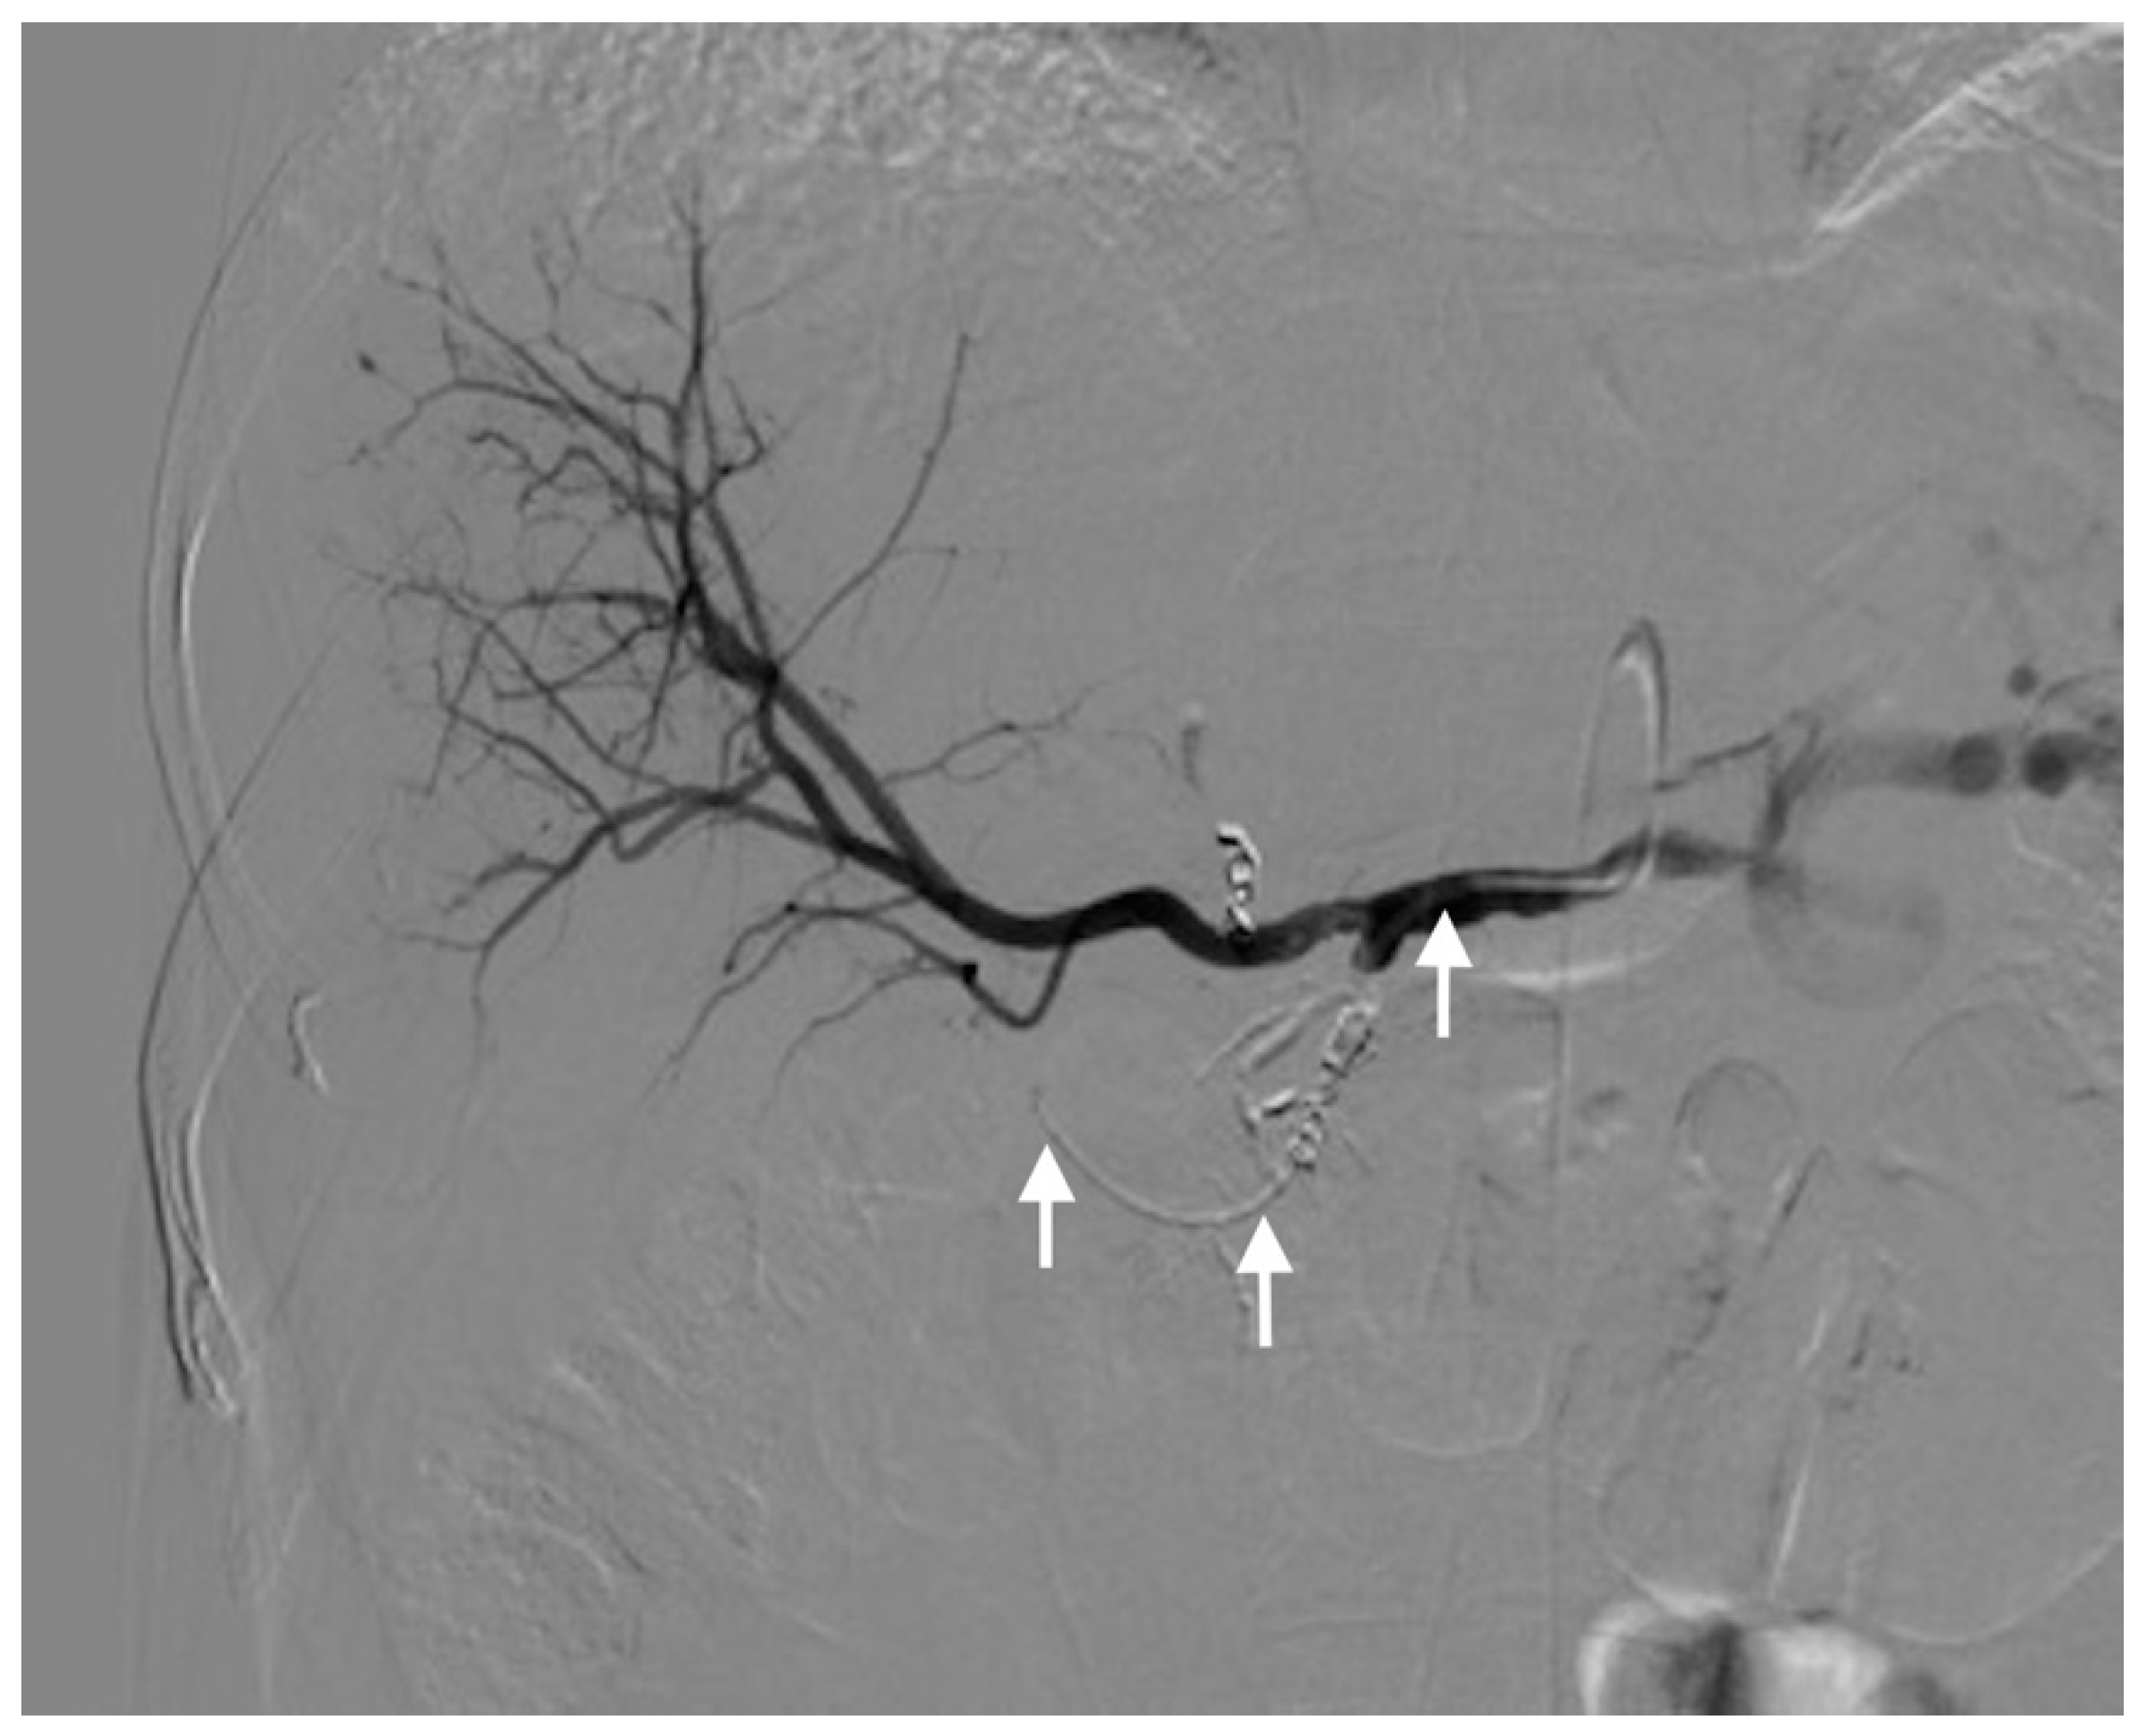

2.2. Percutaneous Microcatheter-Port System Implantation

3.2. Primary Technical Success

3.3. Complications